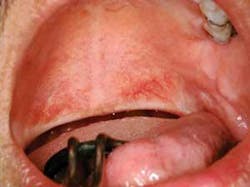

As you begin to talk with Maggie, she tells you that she was viewing her new restorative work in a mirror and believes that some problem has occurred in her posterior throat region. She reports that the area has been irritated since the procedure was completed last week. Maggie asks you if her tonsils and “whatever that thing is that hangs down in my throat” appears irritated. Maggie is referring to the uvula (see Figure 1).

Diagnosis: Maggie has a normal uvula that has an aphthous ulcer present. This is an unusual location but probably has no connection to her previous restorative work and is not due to trauma of the uvula. Because of the location on the uvula, patients may not even know that such a lesion is present other than the discomfort that may be noticed in that area.

Dental implications: The uvula may sometimes become enlarged due to several factors. Infections related to the tonsils, bacterial/viral infections in the throat, allergic type responses, and trauma-related causes. Figure 1 is a good example of the aphthous lesion that has occurred on the uvula presented in this case. The uvula may also be completely removed (uvulectomy) for reasons related to snoring and sleep apnea as seen in Figure 5. Vibration may occur during sleep, producing a snoring sound.